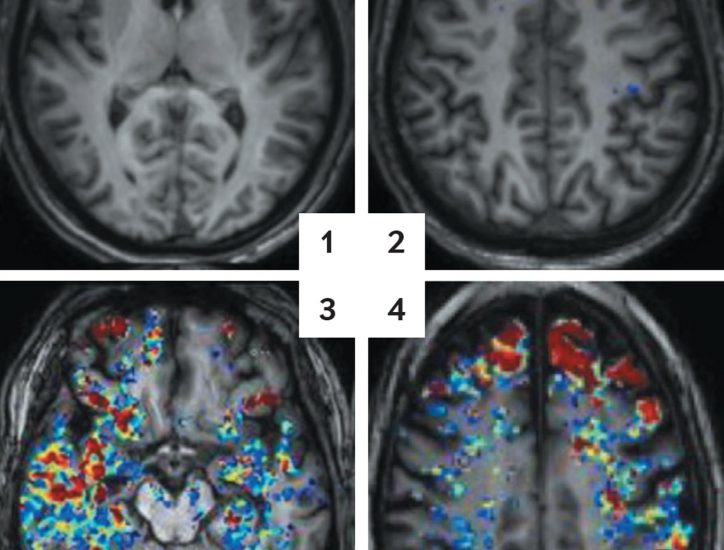

At the forefront of neuroscientific research, the Hebrew University of Jerusalem (HU) is dedicated to advancing our understanding of Alzheimer’s disease and dementia. The institution has been steadfast in its commitment to unveiling the intricacies of cognitive decline and aging. With a rich history of innovative research, HU continues to play a pivotal role in early detection, prevention strategies, and breakthrough therapies for Alzheimer’s and dementia-related disorders.

Cognitive health disorders greatly impact numerous individuals globally, significantly affecting families and communities. At HU, extensive Alzheimer’s and dementia research reveals the nuances of memory loss, cognitive impairment, and the journey from early symptoms to advanced stages.

Understanding the symptoms, early detection, and the various risk factors associated with Alzheimer’s and dementia is the key to transforming patient care. Through a multi-faceted approach, HU research centers continue developing prevention strategies, testing new therapies, and evolving risk assessment tactics to unravel the mysteries of cognitive decline and aging.